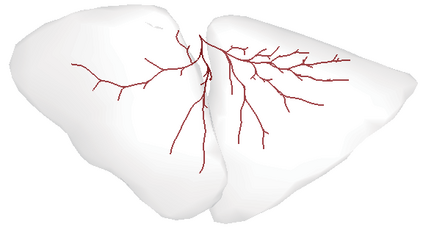

Recent advances in imaging techniques have enabled us to visualize lung tumors or nodules in early-stage cancer. However, the positions of nodules can change because of intraoperative lung deflation, and the modeling of pneumothorax-associated deformation remains a challenging issue for intraoperative tumor localization. In this study, we introduce spatial and geometric analysis methods for inflated/deflated lungs and discuss heterogeneity in pneumothorax-associated deformation. Contrast-enhanced CT images simulating intraoperative conditions were acquired from live Beagle dogs. Deformable mesh registration techniques were designed to map the surface and subsurface tissues of lung lobes. The developed framework addressed local mismatches of bronchial tree structures and achieved stable registration with a Hausdorff distance of less than 1 mm and a target registration error of less than 5 mm. Our results show that the strain of lung parenchyma was 35% higher than that of bronchi, and that subsurface deformation in the deflated lung is heterogeneous.